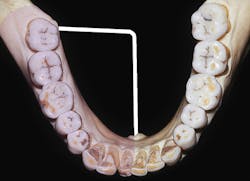

The target area or deposit location for the V-A block is the medial surface of mandibular ramus within the pterygomandibular space approximately halfway between the mandibular foramen and the neck of the mandibular condyle, as well as being adjacent to the maxillary tuberosity (see Figure 4 and procedure sidebar).

Figure 4: Target area for the Vazirani-Akinosi mandibular block is the medial surface of the mandibular ramus within the center of the pterygomandibular space (A) at approximately halfway between the mandibular foramen and neck of the mandibular condyle (dashed line with circle) (B) as well as being adjacent to the maxillary tuberosity (C).2,3 (courtesy of Saunders/Elsevier)